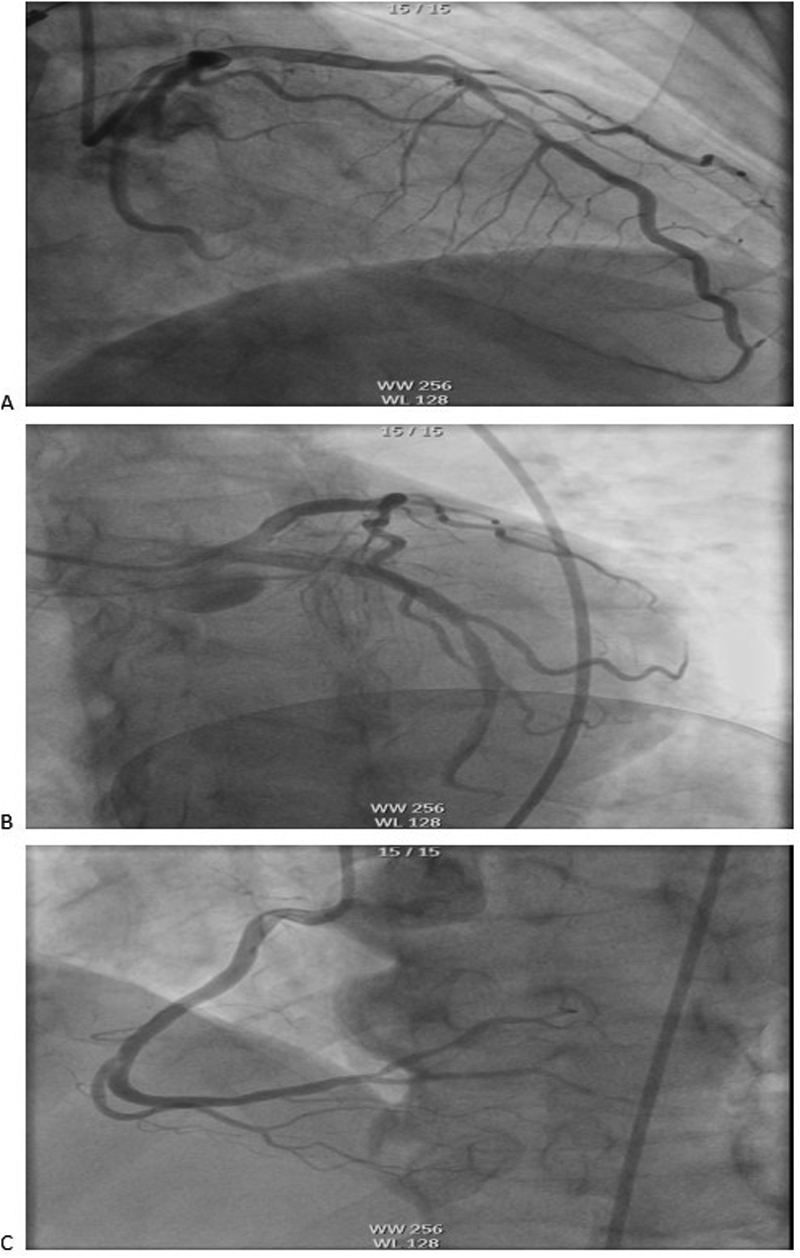

The electrocardiogram (ECG) revealed VPCs, prolonged QTc interval, and ST-T wave changes. Portable transthoracic echocardiography (TTE) revealed global ventricular hypokinesis. Laboratory findings included: Hypersensitive troponin T (hs-TnT): 0.191 ng/ml (ref. ≤0.014 ng/ml); Troponin I (TnI): 0.12 ng/ml; Creatine kinase-MB (CK-MB): 4.3 ng/ml; B-type natriuretic peptide (BNP): 443 pg/ml (ref. <100 pg/ml); D-dimer:526 ng/ml. During emergency department evaluation, the differential diagnoses included coronary artery disease, viral myocarditis, and entrectinib-induced myocarditis. Emergent coronary angiography demonstrated no significant stenosis in the three major coronary vessels: the left anterior descending artery (LAD), left circumflex artery (LCX), and right coronary artery (RCA) (Figure 1).

Figure 1

Coronary angiography showed no obvious stenosis in the coronary arteries: (A) LAD, (B) LCX, (C) RCA. LAD, left anterior descending artery; LCX, left circumflex artery; RCA, right coronary artery.